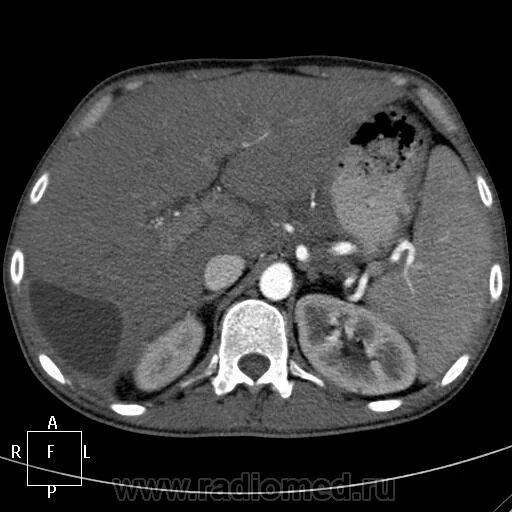

Образования печени кт